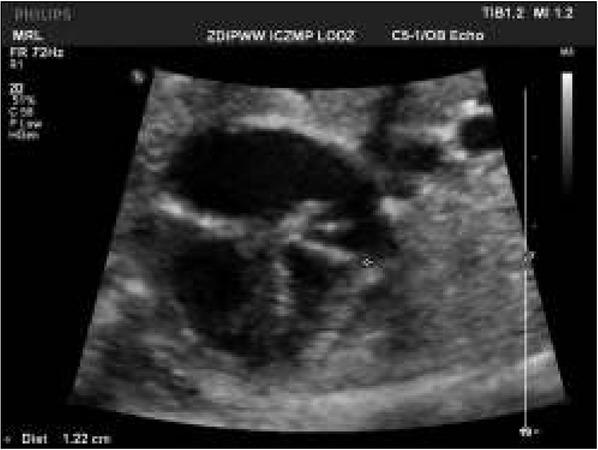

Fig. 4

Abnormal view of the fetal heart at 29th week of gestation with pericardial effusion of 5 mm – one of the signs of congestive heart failure and fibroelastosis of enlarged left ventricle.Ryc. 4. W 29 tyg. nieprawidłowy obraz serca płodu z cechami niewydolności krążenia – wysięk w osierdziu 5 mm oraz fibroelastoza powiększonej lewej komory serca.